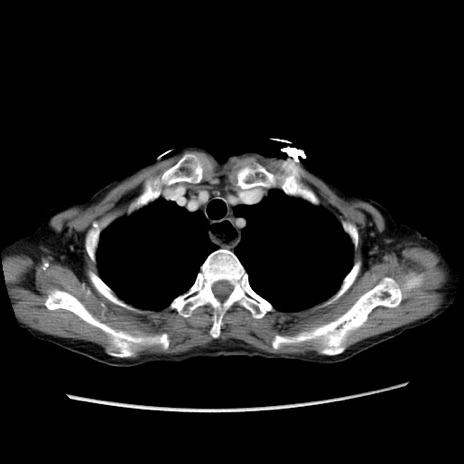

症例25(横断像)

【症例】80歳代女性

【主訴】胸のつかえ感

【現病歴】約9時間前に食後から胸のつかえた感じあり、嘔吐あり、来院。

【既往歴】胃癌(全摘)、胆摘、虫垂炎

【身体所見】心窩部に圧痛あり、反跳痛なし。

【データ】WBC 5700、CRP 0.05